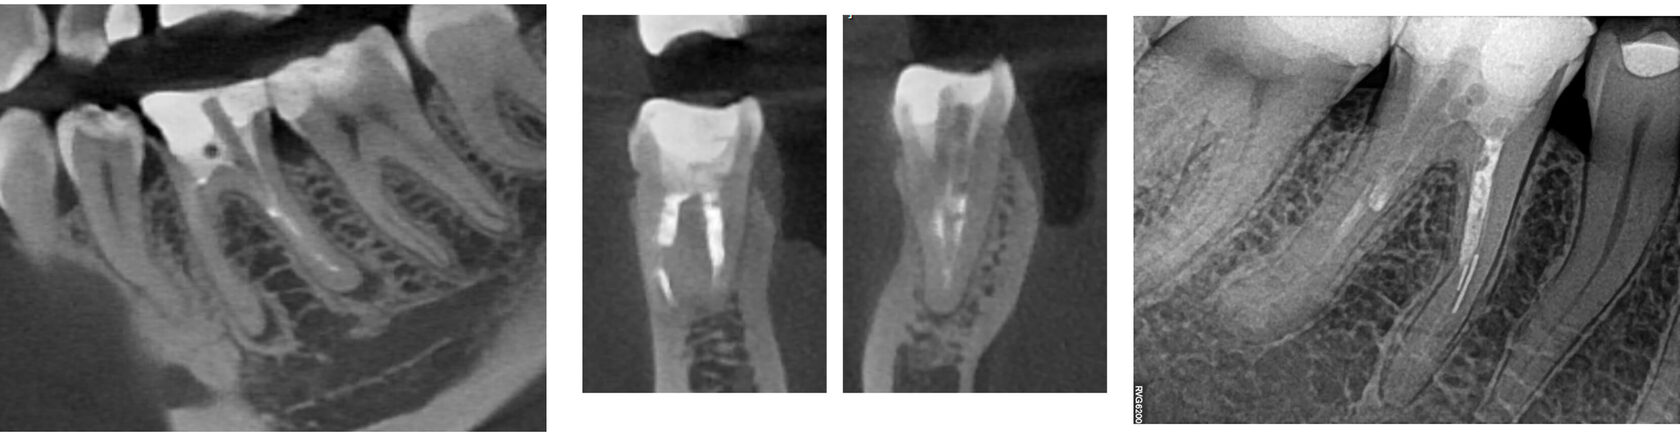

3. Пациентка нарушила график приемов, повторное обращение в клинику через 10 месяцев после начала лечения: временная пломба сохранена, временный обтурационный материал сохранен в корневых каналах, по КЛКТ отмечается значимое уменьшение очага перирадикулярной деструкции. (Фото 5,6,7)

4. Завершение эндодонтического лечения, корневые каналы обтурированы, зуб восстановлен под ортопедическую конструкцию. (Фото 8)